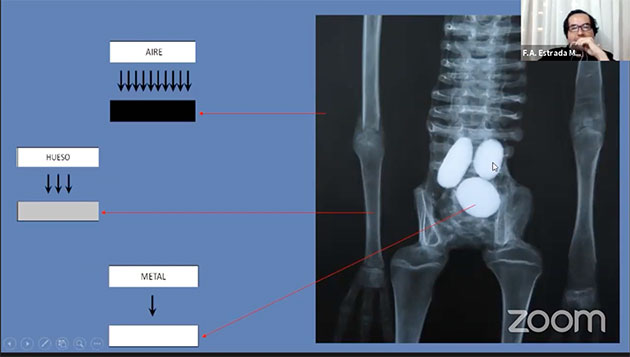

Ab Timecode 1.06:12 geht Moreno nochmals auch die Röntgenanalysen einiger Mumien ein und zeigt, wie sich die unterschiedlichen Materialien (Aire = Luft, Grasa = Fett, Agua = Wasser, Hueso = Knochen und Metall, s. Abb. 64) in der Röntgenbetrachtung abbilden.

Interessant wird die Frage angesichts der kleinen Mumie (Josefina) mit den drei vermeintlichen Eier im Bauch (s. Abb. 39-43). Anhand der Röntgenaufnahme müssten die drei „Eier“ eigentlich aus Metall oder Stein sein, da sie sich wesentlich heller abzeichnen als die Knochen (s. Abb. 65).

Diese Beobachtung widerspricht allerdings der Behauptung des Biologen Lopez, der im Auftrag von Gaia zuvor die Mumie untersucht und erklärt hatte, es sei ihm gelungen, mit einer Nadel in eines der Eier einzudringen. Morales glaubt dies nicht, da dies bei der festen Zusammensetzung der Gebilde (Stein oder Metall) nicht möglich sei. Morales (der Lopez grundsätzlich einen „Pseudowissenschaftler“ bezeichnet; Lopez selbst ist auch einer der Autoren der taxonomischen Beschreibungen der den Mumien – siehe Abb. 09) vermutet, dass der Einstich „zwischen“ und nicht „in“ die Eier vollzogen wurde. Tatsächlich zeichnen sich selbst auf Lopez‘ eigener Röntgenaufnahme (die den Einstich dokumentieren soll, s. Abb. 66), die Eier heller (und damit dichter) als die Nadel (Aguja) selbst ab. Die Vorstellung, dass diese Nadel in diese „Eier“ eingedrungen sein soll, sei also „absurd“ so Morales.